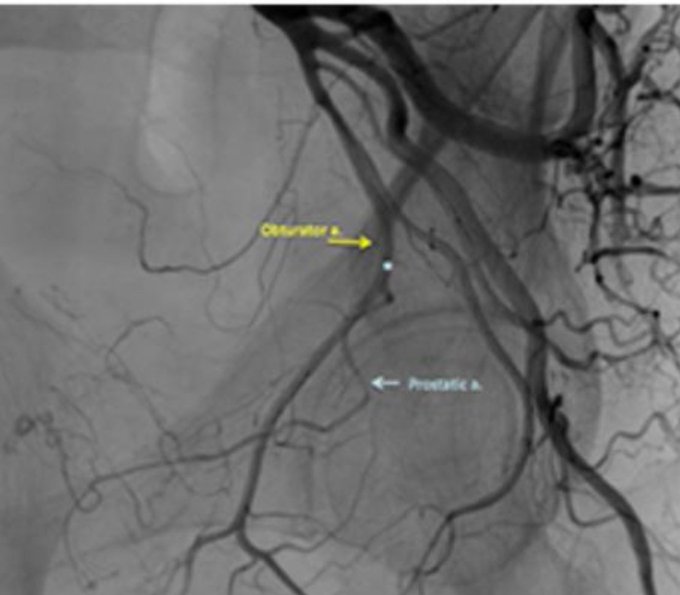

3️⃣الأغلاق للانتقائي لشريان البروستات

PAE

ايضل يتم بدون تخدير عن طريق اغلاق الشريان المغذي للبروستات مما يؤدي لصغر حجمها